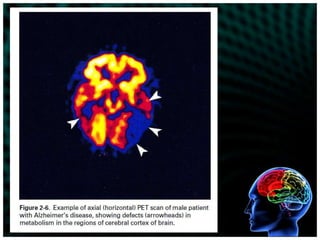

Detailed patient history with corroboration by an informed sourceto determine cognitive and behavioral changes, their duration, and symptoms that may be indicative of other medical or psychiatric illnessesNoncontrast computed tomography (CT) scan, Magnetic resonance imaging (MRI),  single-photon emission computed tomography (SPECT) to rule out other neurologic conditionsNeuropsychological evaluation (mental status assessment)to identify specific areas of impaired mental functioning in contrast to areas of intact functioning

Detailed patient historywith corroboration by an informed sourceto determine cognitive and behavioral changes, their duration, and symptoms that may be indicative of other medical or psychiatric illnessesNoncontrast computed tomography (CT) scan, Magnetic resonance imaging (MRI), single-photon emission computed tomography (SPECT) to rule out other neurologic conditionsNeuropsychological evaluation (mental status assessment)to identify specific areas of impaired mental functioning in contrast to areas of intact functioning